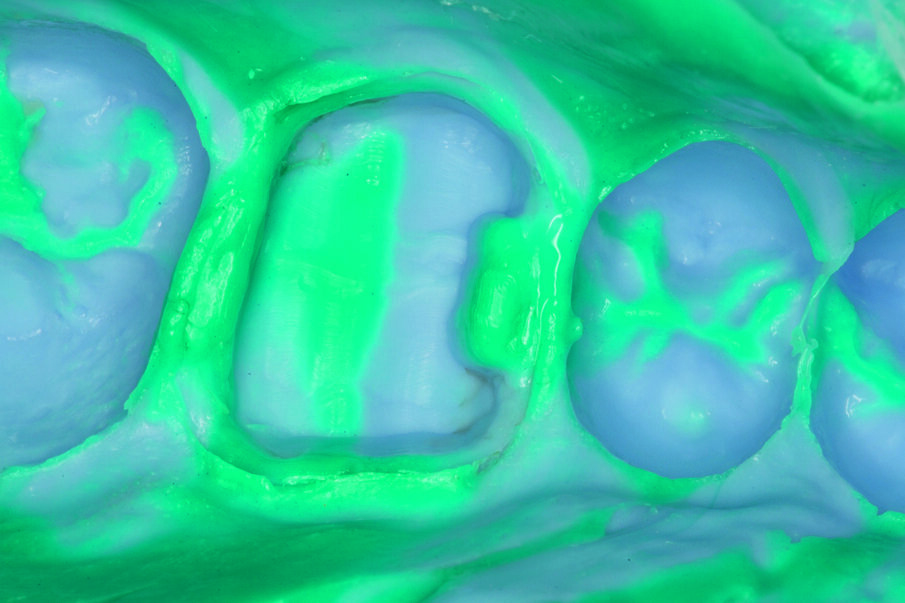

Fig. 7: Impression taking with Aquasil® Ultra Putty soft and Aquasil® Ultra Light LV.